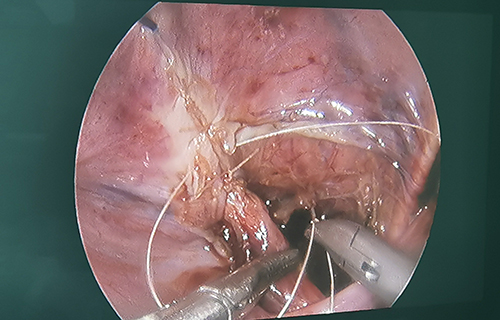

术前准备完毕。10月15日,栾志勇主任、谢方达副主任为佳佳行输尿管远端狭窄微创手术,在其肚脐周围打了3个直径5mm的小孔,在腹腔镜下顺利实施了输尿管膀胱再植。手术用时仅为3小时,出血量也比较少。

“如果开刀手术,需要在腹部做横切口,对孩子的损伤是比较大的。在保证手术效果的基础上,微创手术对孩子的损伤小,美观程度良好,术后恢复比较快。”栾志勇主任说。

腹腔镜下输尿管膀胱再植手术的成功,标志着啪啪网 针对泌尿外科疾病的治疗完全实现微创个体化,涵盖肾脏及肾上腺实体肿瘤、囊性病变、肾盂积水、重复肾脏、输尿管膀胱反流、输尿管梗阻等上、下尿路重建的重症及常见病的治疗,也标志着啪啪网 泌尿外科治疗达到东北地区领先水平。